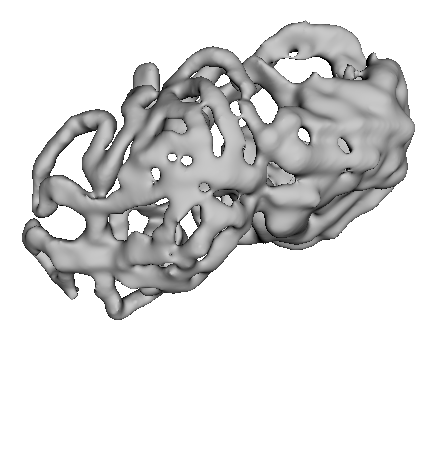

Figure 3 shows example segmentation results in 3D. The result corresponding to ‘feat. & out. level DA’ in Table 1 is compared to ours. We note that the only difference between them is whether the feature disentanglement is involved for the domain adaptation, thus could show its effectiveness. Fewer errors are observed for the proposed method. We believe this is because the proposed method explicitly concentrates on the features more transferable across the datasets, the non-intensity features in this work, by disentangling those features and applying adversarial learning directly to them during the adaptation process. Example reconstruction results from the auto-encoding architecture as well as segmentation results in coronal view can be found in supplementary material.

A

B

B

C

C